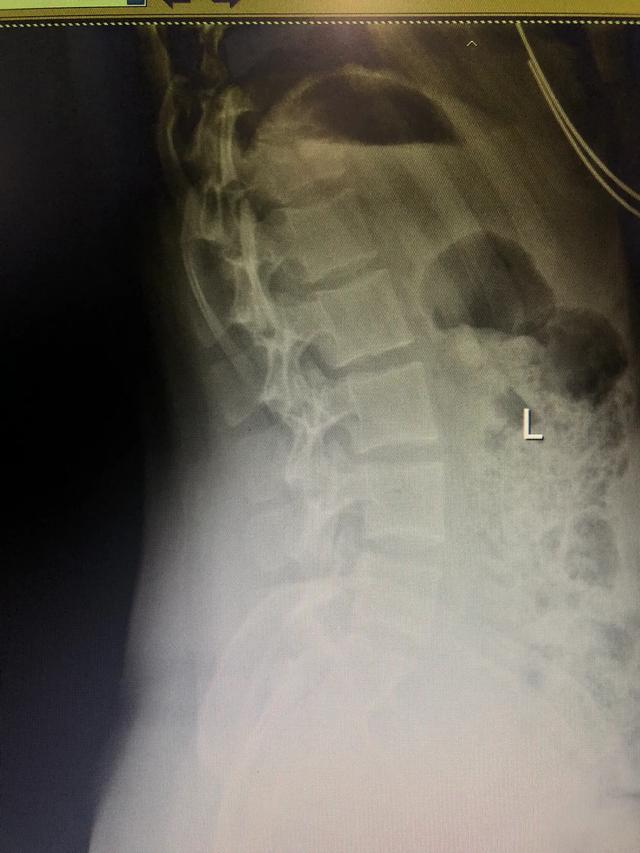

X片看到第一腰椎变扁